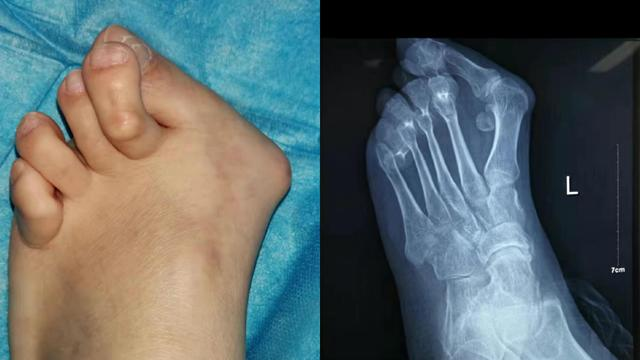

x光片更直观了解大脚骨 如果单纯去掉凸起能否有效矫正拇外翻呢?

大脚骨手术术后照片,手术非常成功#大脚骨 #门诊 #矫形 - 抖音

俗称"大脚骨",现行右足矫形,软组织,籽骨松解复位 chevron截骨 关节囊